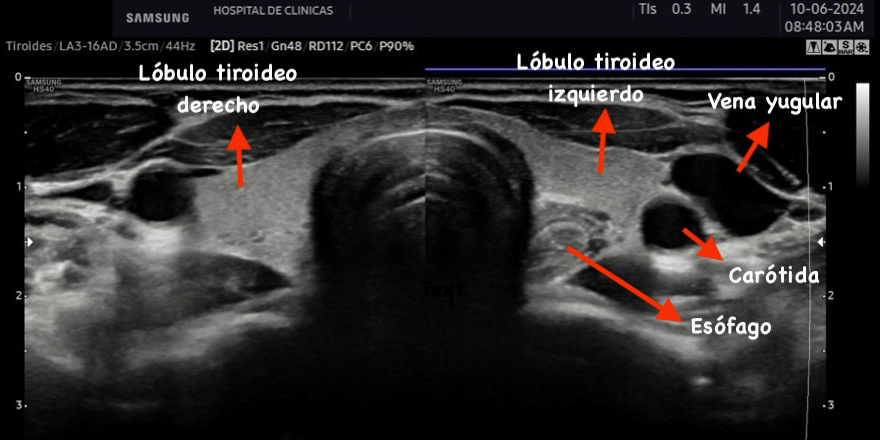

Figura 2: Corte transversal de la tiroides normal, se señalan con las

flechas distintas estructuras.

La tiroides de un adulto tiene un tamaño variable de aproximadamente 13 a 18 mm de ancho o transversal (T), 16 a 18 mm de profundidad o anteroposterior (AP) y 45 a 60 mm de largo o longitud (L), el istmo mide entre 2 a 6 mm de profundidad (AP). El volumen del lóbulo se calcula mediante la fórmula V (ml) = 0,479 × AP × T × L (cm). El número 0,479 o 0,524 en la fórmula es el factor de corrección para determinar el volumen de estructuras de una forma elipsoide, existen varias constantes y puede utilizarse cualquiera de ellas. El volumen de la tiroides es la suma de los volúmenes de ambos lóbulos. El volumen del istmo por ser pequeño, en general inferior a 10 mm no está incluido2. El volumen de una tiroides normal tanto en adultos como en niños es fuente de debate. La Organización Mundial de la Salud sugiere un volumen normal en hombres de 7,7 a 25 cm3 y en mujeres de 4,4 a 18 cm3(2). Depende de la edad y el área de superficie corporal de cada individuo2.

La ecogenicidad es media o alta cuando se compara respecto a los músculos pre tiroideos, tiene aspecto granular fino similar a las glándulas salivales y es isoecoica respecto a estas últimas. Cuanto más coloide y menos células haya en la glándula se produce mayor reflexión del sonido, por lo tanto, mayor ecogenicidad con respecto a los músculos pre tiroideos y demás tejidos como se observa en la figura 26.

La eco estructura es homogénea, los márgenes son regulares y presenta una cápsula ecogénica, su vascularización es escasa. El rango de referencia para una tiroides normal es de entre cinco y diez vasos visibles dentro de la exploración de cada lóbulo valorado con Doppler color2. Se ha descripto que hasta un 50% de los individuos presentan lóbulo piramidal (Figura 3a y 3b). Este sector, en general, es similar en ecogenicidad, homogeneidad y vascularización al istmo y los lóbulos. En la superficie posterior de los lóbulos tiroideos, especialmente en el segmento inferior, puede visualizarse el tubérculo de Zuckerkandl, un ejemplo de este se puede observar en la figura 4a y 4b. Este es un tabique hiperecogénico fibroso que a menudo genera sombra posterior. Se forma por la extensión del tejido tiroideo de las áreas laterales de los lóbulos hacia el sector posterior, y a menudo exhibe una disminución de la ecogenicidad detrás del mismo. Este proceso puede imitar una lesión tiroidea o paratiroidea y causar dificultades en la interpretación2.